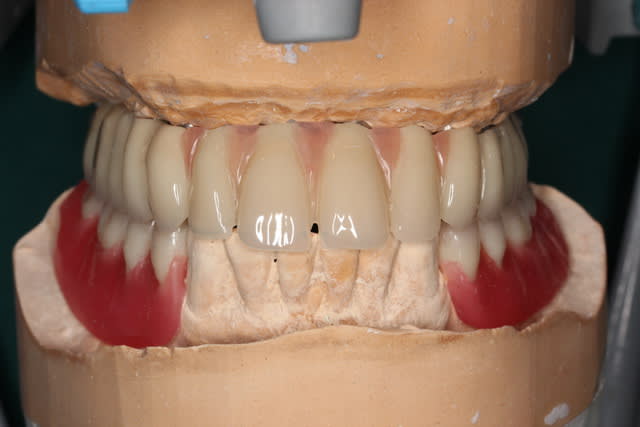

Img 1182 s6mmza - Eugenol

Img 1193 e1whny - Eugenol

Img 1194 xpaov4 - Eugenol

Manque que 6 e.max en antérieur !

merci pépé

De rien flic flac et désolé pour le retard ;-)